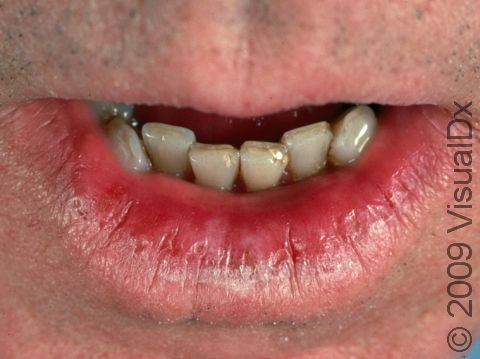

Actinic Cheilitis

Actinic cheilitis, sometimes known as “farmer’s lip” or “sailor’s lip,” is a precancerous condition related to cumulative lifetime sun exposure. The lower lip is most often affected. Individuals with actinic cheilitis often complain of persistent dryness and cracking of the lips. They will frequently exhibit other effects of sun-damaged skin, such as precancerous lesions on the skin called actinic keratoses and extensive wrinkling.

Actinic cheilitis is located on the lips, most often the lower lip. Persistent redness, scaliness, and chapping are among the symptoms noted. Erosions and cracks (fissures) may be present as well.